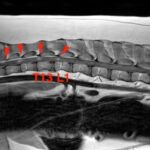

• 【MRI、胸腰部矢状断像、T2強調画像】

画像で見る病気(飼い主様向け)

#19 変性性腰仙椎狭窄症(馬尾症候群)(飼い主様用)

<症例情報> ゴールデンレトリーバー10歳 去勢済みの男の子 主訴:最近腰のあたりを触られ…